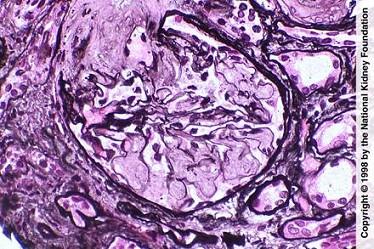

问题 如图,银染色可见系膜区及毛细血管袢有淀粉样物质沉积,刚果红染色呈砖红色阳性,电镜以淀粉样纤维沉积为特点,其病理诊断可考虑为 ( )

选项 A.糖尿病肾病 B.高血压肾损害 C.肾淀粉样变性 D.乙肝相关性肾炎 E.肾小球肾炎

答案 C